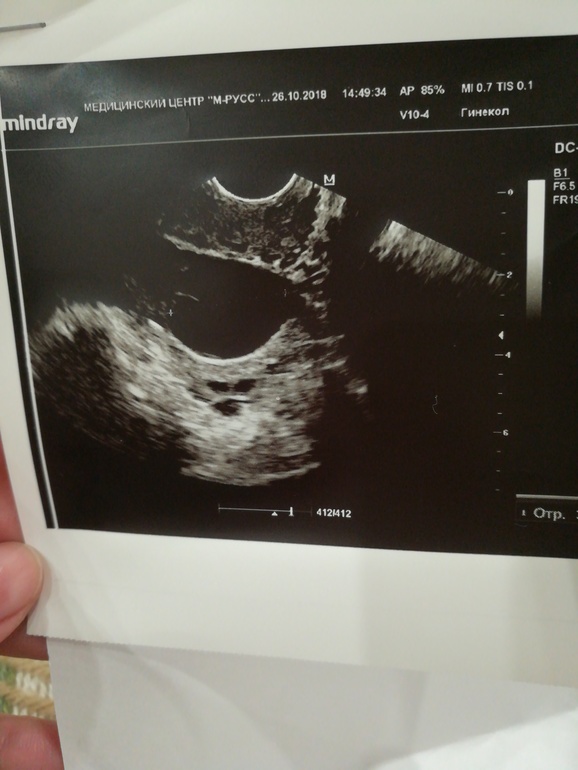

Киста яичника. ЖТ нет. Врач узи еще какой то бестолковый попался. Нормально не смог дать ответы

Фолликулярная киста. Простите

Может узистка ошиблась и овуляция все таки была

думаю, что нет(

А по картине будто она только пару часов назад была. Посмотри в интернете.